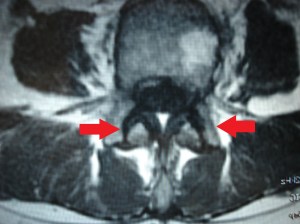

Las imágenes a continuación pertenecen a un caso con una remisión sintomática casi completa y un grado muy alto de satisfacción de la paciente tratada.

En las imágenes de RX y RMN se observan los cambios degenerativos (señalados en rojo las articulaciones interapofisarias artrósicas), también la presencia de múltiples hemangiomas, y las imágenes intraoperatorias de control de los implantes de oro (con flechas).